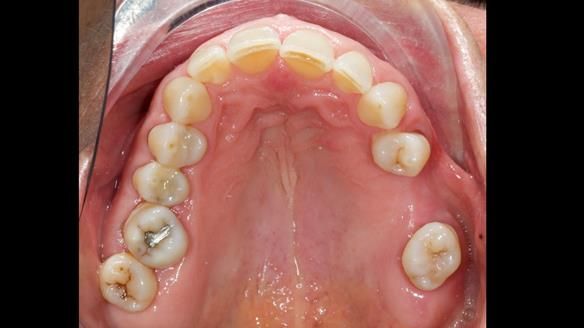

Joyce's Case Presentation 61

Welcome to Newsletter 61. In this edition, I walk through the process of creating and fitting a metal based lower partial denture for Joyce, a fit and healthy 76 -year-old woman.

Joyce self-referred to me for specialist prosthodontics.

The missing lower right teeth to be replaced with a metal based partial denture.

The detailed clinical situation and treatment process are outlined below, with clinical work provided by me and technical work by Rowan Garstang. The treatment spanned six visits for denture fitting and one review.